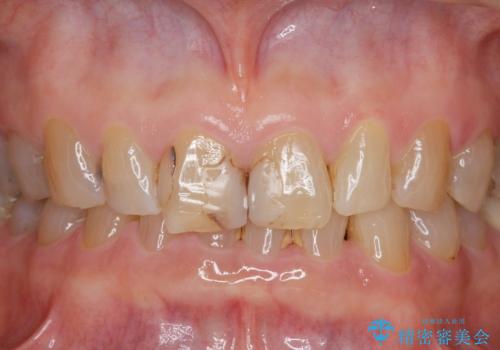

- 前歯の小さな虫歯を複数回治療した結果、つぎはぎだらけになってしまい審美的な改善を求めて来院されました。

これ以上のコンポジットレジン修復は更なる審美障害を招きかねないので、全体を覆うセラミッククラウンを選択します。

ディープバイト・噛み合わせが強いことからフルジルコニアクラウンを選択しました。